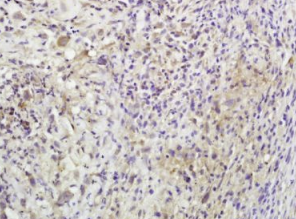

组织/细胞:小鼠淋巴瘤;4%多聚甲醛固定石蜡包埋;

抗原提取:柠檬酸缓冲液(0.01M,pH 6),15min煮沸,用3%过氧化氢阻断内源性过氧化物酶30min;37℃下阻断缓冲液(正常山羊血清)20 min;

孵育:抗β-内啡肽多克隆抗体,未结合1:600,在4°C下过夜,然后与二级抗体结合,DAB染色。